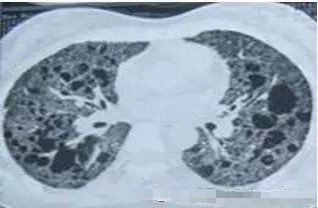

4. 王医生,你看,这个人到处都是GGO,怎么办?

元芳,你仔细看,它是弥漫性的磨玻璃影,这是肺淋巴管平滑肌肌瘤病,不是肺癌,不用担心。